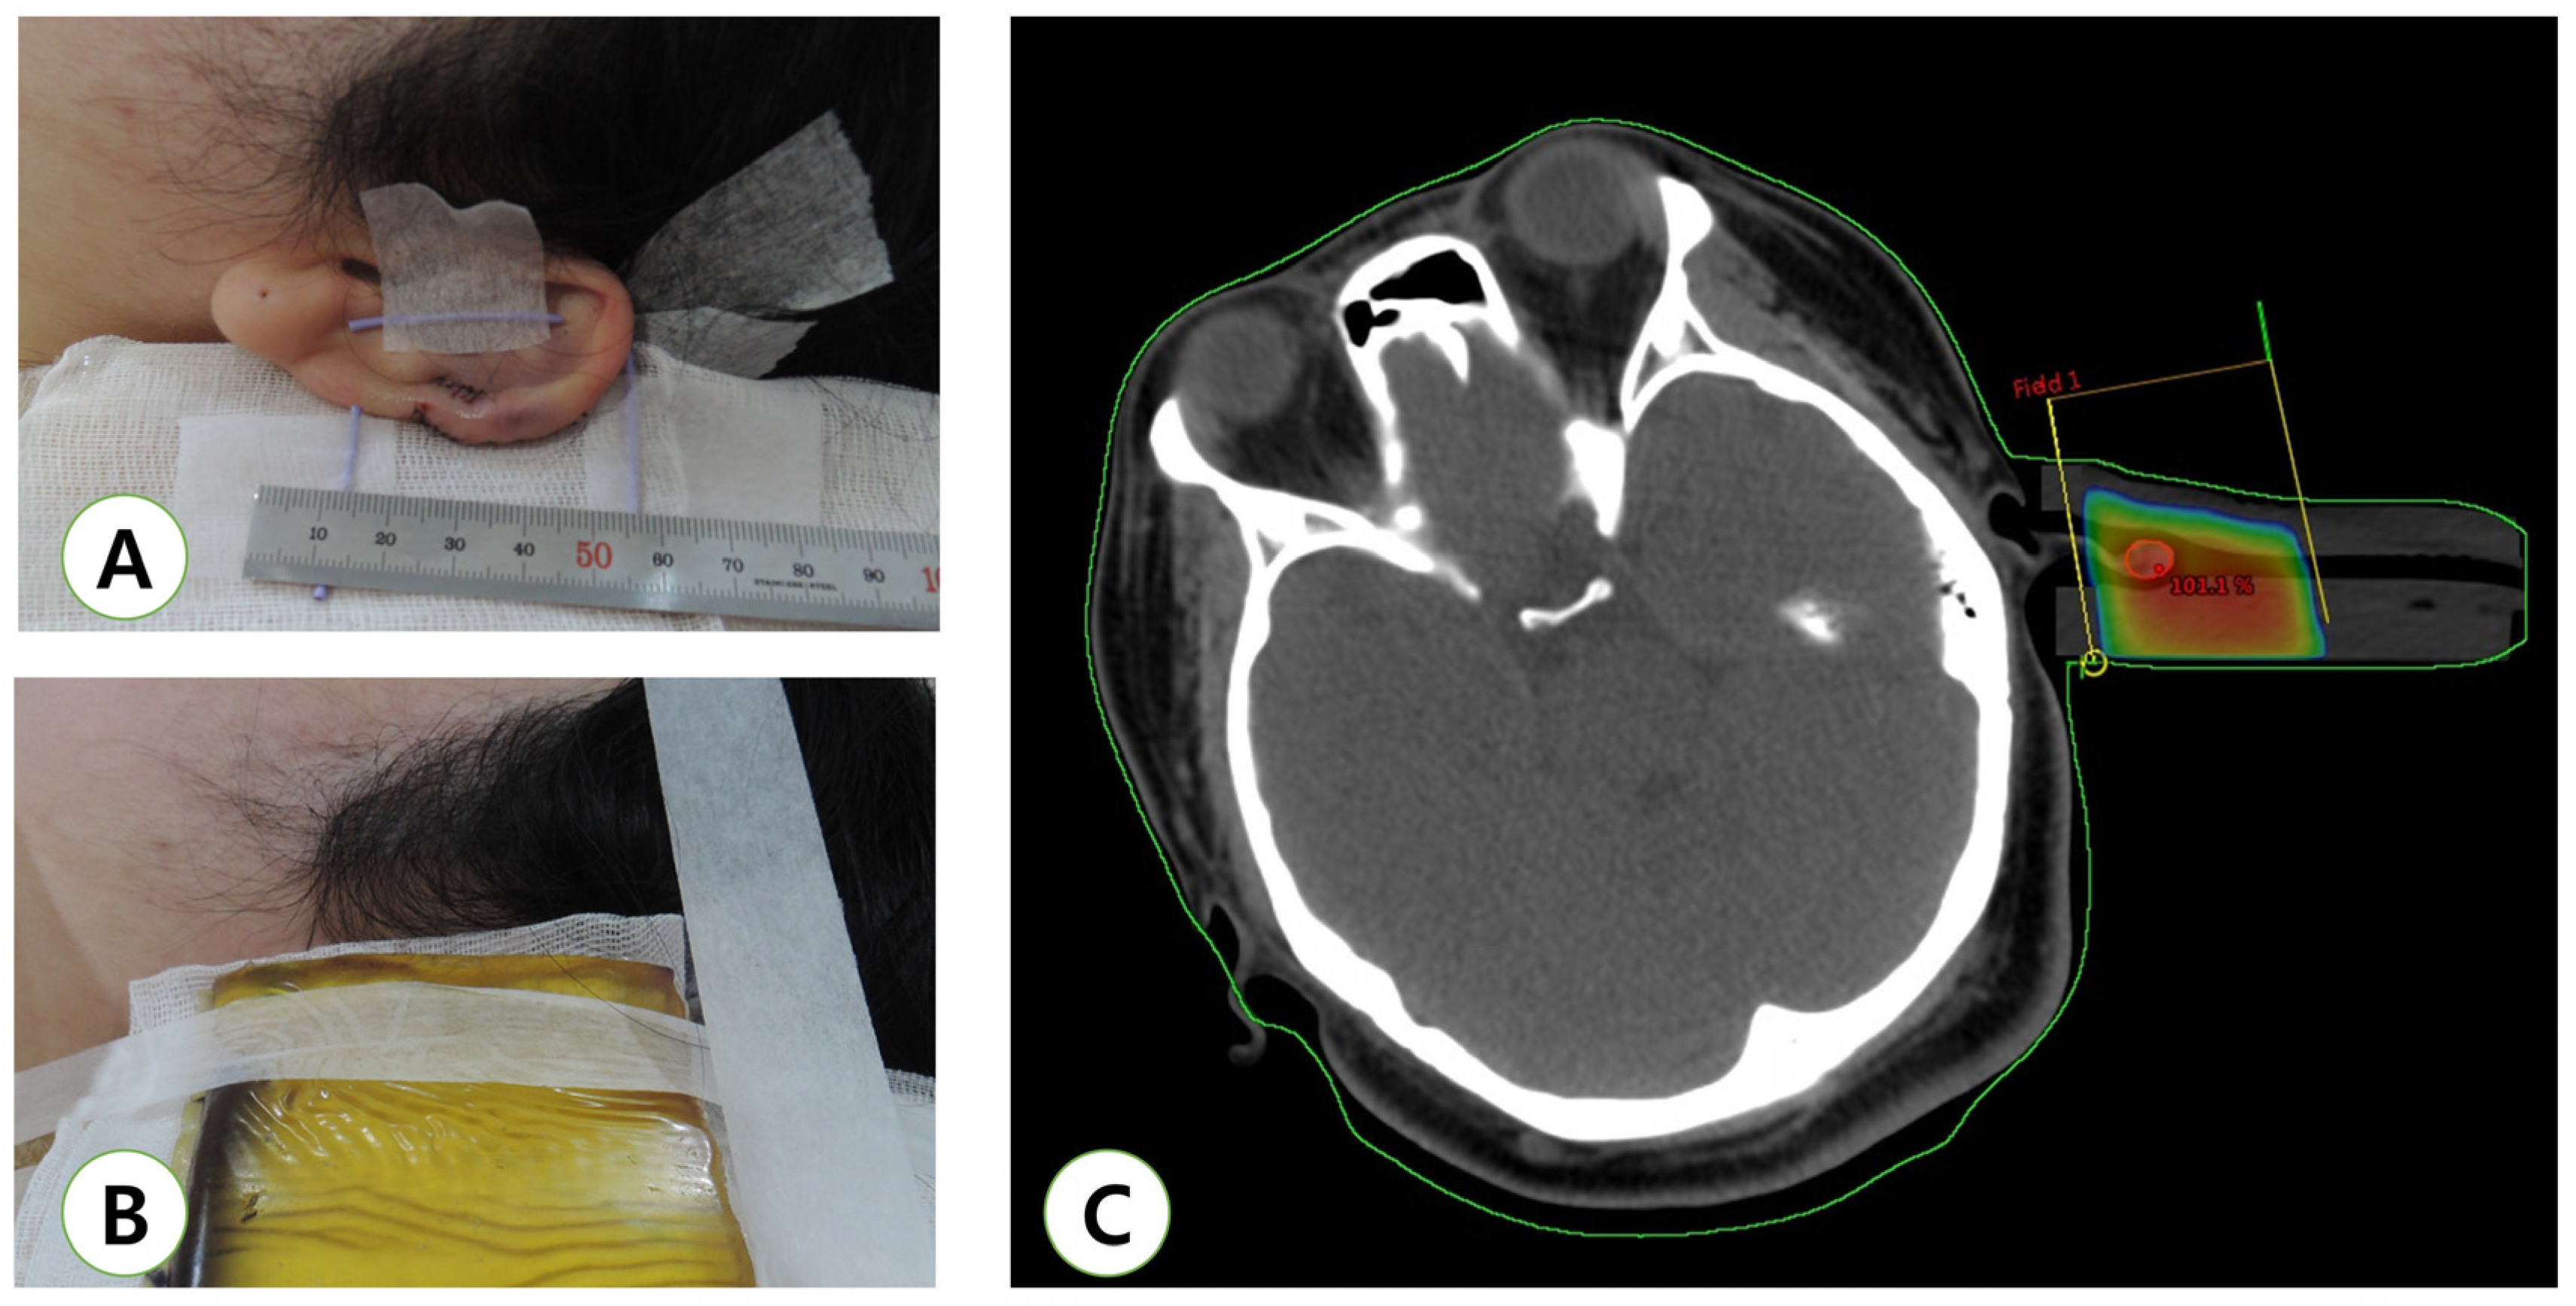

4. Radiation Technique

- Hsueh, W.T.; Hung, K.S.; Chen, Y.C.; Huang, Y.T.; Hsu, C.K.; Ogawa, R.; Hsueh, Y.Y. Adjuvant Radiotherapy After Keloid Excision: Preliminary Experience in Taiwan. Ann. Plast. Surg. 2019, 82, S39–S44. [Google Scholar] [CrossRef]

- Lin, Y.F.; Shueng, P.W.; Roan, T.L.; Chang, D.H.; Yu, Y.C.; Chang, C.W.; Kuo, A.T.; Chen, Y.S.; Hsiao, H.W.; Tien, H.J.; et al. Tomotherapy as an Alternative Irradiative Treatment for Complicated Keloids. J. Clin. Med. 2020, 9, 3732. [Google Scholar] [CrossRef]